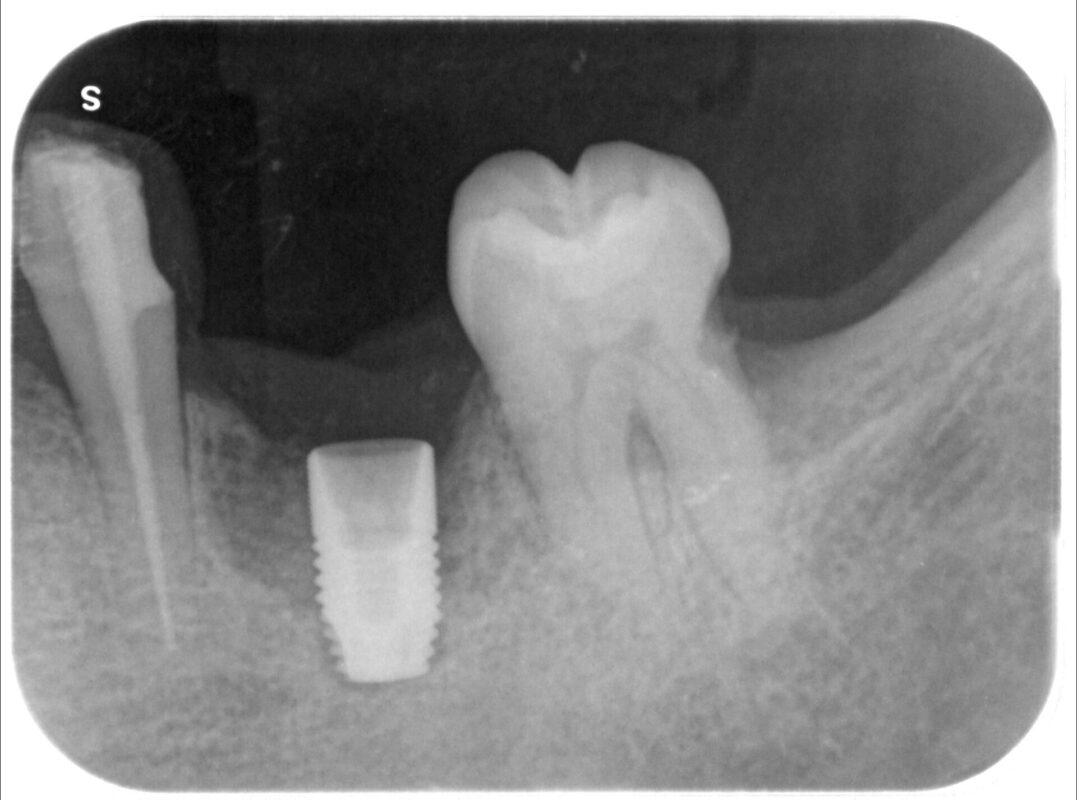

軟組織を増やす処置を行なったため、3ヶ月ほど待機してインプラント処置しました。

少し人工骨を添加しています。

処置時間は15分程度です。

4ヶ月程度待ってから仮の歯を装着するための2次オペ予定。

使用インプラントはアストラEV(スウェーデン)。